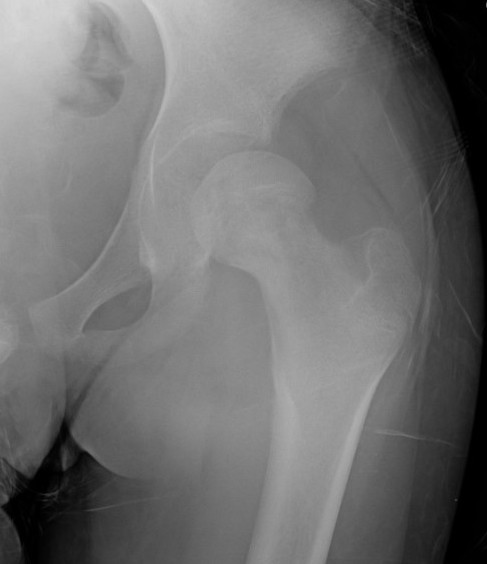

Xray

Normal with transient synovitis

Hip subluxation with septic arthritis

Septic arthritis

SCFE / Perthes